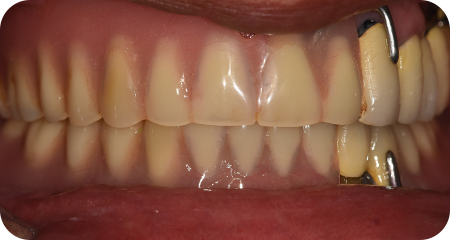

CASE 02

58세 / 남

상악 다수 임플란트, 하악 부분 임플란트

초진 당시 상악 다수 치아 상실로 식사 시 어려움을 겪으셨던 환자분

하악도 어금니 상실과 충치 치료가 필요했던 상황이었습니다.

잇몸치료, 충치치료를 통해 최대한 치아를 보존하고 상실된 부위 다수 임플란트를 진행하였습니다.

치료 중간 내원을 못 하셨던 기간이 있었지만 다행이 안정적으로 임플란트를 마무리하였습니다.

치료기간 : 2021.11.23 ~ 2023.07.01

BEFORE

AFTER